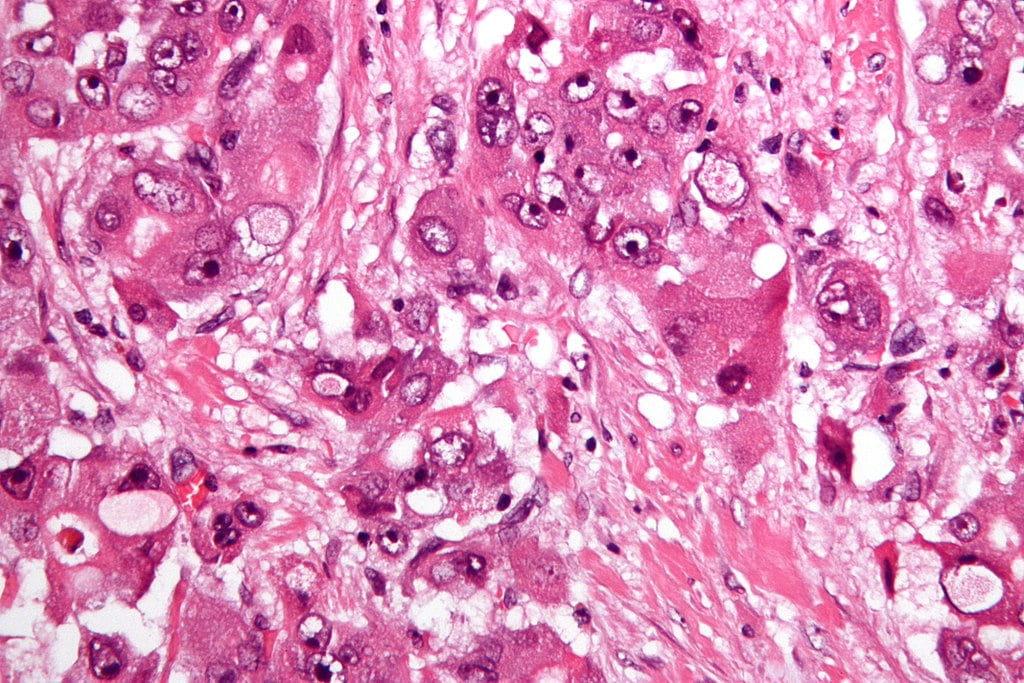

Desi multe simptome si investigatii pot confirma existenta cancerului hepatic, acesta poate deveni un diagnostic de certitudine dupa ce este efectuata biopsia hepatica. In urma analizei fragmentului de tesut extras la microscop se va stabili stadiul cancerului, tipul si gravitatea acestuia.